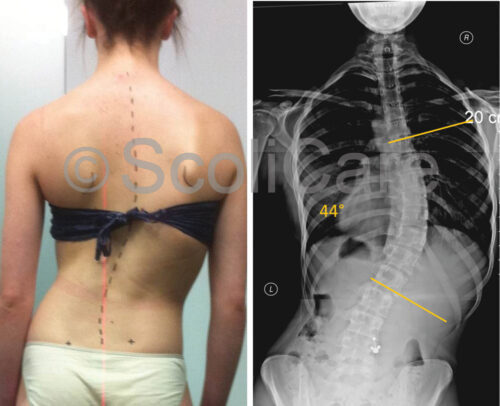

يعاني بعض المراهقين من اعوجاج العمود الفقري، وهو انحناء جانبي للظهر يظهر غالبًا خلال مرحلة النمو السريع. كثير من الأهل يتساءلون: هل يؤثر هذا الانحناء على الحوض؟ وهل يمكن للحوض أن يغير من طريقة وقوف الطفل أو حركته؟ في هذا المقال نشرح نتائج الدراسات الحديثة بطريقة مبسطة، ونجيب على أهم الأسئلة التي تشغل الأهل.

الدراسات الحديثة قارنت بين نوعين شائعين من الانحناءات عند المراهقين:

الانحناء الصدري الكبير: وهو انحناء في منتصف الظهر باتجاه اليمين غالبًا.

الانحناء السفلي الكبير (القطني أو القطني-الصدري السفلي): وهو انحناء في أسفل الظهر غالبًا إلى اليسار.

أظهرت النتائج أن:

معظم المراهقين الذين لديهم انحناء صدري يميل الحوض لديهم أيضًا قليلًا باتجاه نفس جهة الانحناء، أي يميل إلى اليمين.

المراهقون الذين لديهم انحناء سفلي يميل الحوض لديهم أيضًا غالبًا باتجاه جهة الانحناء، أي إلى اليسار.

ميل الحوض كان أكثر وضوحًا عند الأطفال المصابين بانحناء صدري مقارنة بمن لديهم انحناء سفلي.